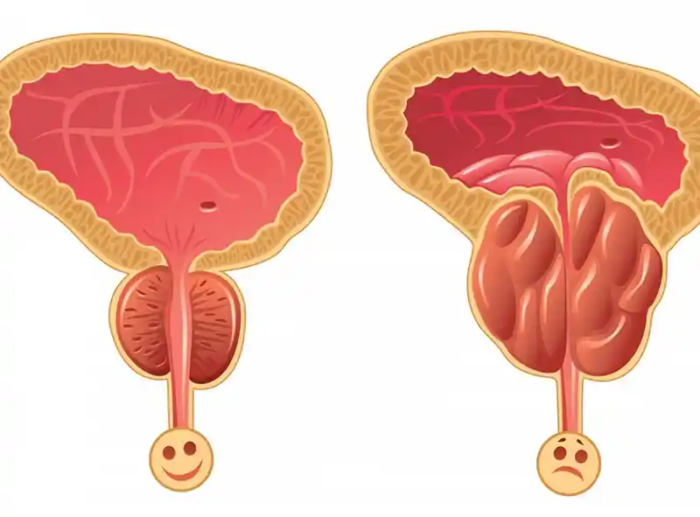

This walnut-shaped gland surrounds the urethra, the tube through which urine flows, and is part of the male reproductive system.

The prostate gland starts off small and has two main phases of growth. It doubles in size during adolescence and continues to grow again after the age of 25 for the rest of a man’s life.

However, an excessively enlarged prostate can lead to a condition known as benign prostatic hyperplasia (BPH). Ultimately, an enlarged prostate can press on the urethra and restrict urine flow from the bladder.

This leads to problems such as:

- frequent urination

- difficulties urinating

- urine leakage

- urinary tract infections